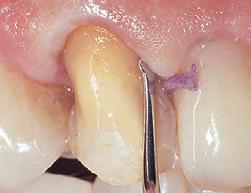

1. Subgingival preparation with bleeding. BLEEDING HEMOSTASIS

2. Scrub Astringedent™ X hemostatic firmly against bleeding tissues with Metal DentoInfusor™ tip.

CLEANING/TESTINGDISPLACEMENT

3. Firm air/water spray removes residual

and tests tissue for quality, profound hemostasis.

Remove

4. Soak Ultrapak™ knitted cord in Astringedent™ X hemostatic, pack, and leave for 5 minutes.